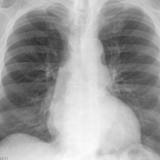

Cardiomegaly, esp RA PA

Date: 01/26/2009

Views: 2921